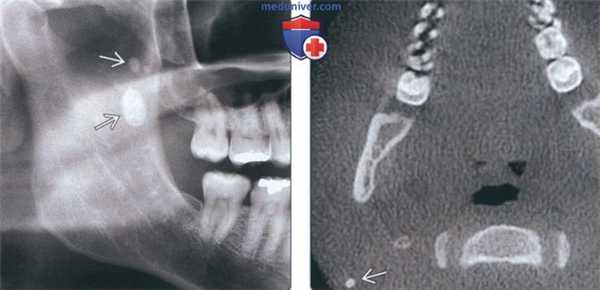

На ортопантомограмме выявлено наличие полуретенированного третьего моляра (зуб мудрости, зуб 38) (рис. 2) . Дистально от зуба 38 определяется наличие очага разряжения костной ткани размером 10 мм, образовавшегося вследствие увеличения фолликула зуба 38.

Рис. 1. Клинический вид абсцесса околоушной области. Гнойный лимфаденит латеральных шейных лимфатических узлов, появившийся после проведения дистанционной ударно-волновой литотрипсии по поводу лечения предполагаемого сиалолитиаза. Рис. 2. Ортопантомография выявила аномалию прорезывания зуба 38 и наличие фолликулярной кисты.

(Слева) На кадрированной панорамной рентгенограмме в правой околоушной железе визуализируются множественные сиалолиты различного размера, которые необходимо дифференцировать с кальцинатами в небной миндалине и обызвествленными лимфоузлами. Последние обычно имеют неправильную форму и напоминают цветную капусту. Относительно часто встречаются множественные сиалолиты.

(Справа) На кадрированной аксиальной КЛКТ визуализируется сиалолит в задних отделах паренхимы правой околоушной железы. Примерно 17% сиалолитов околоушной железы расположены интрапаренхиматозно. (Слева) На обработанной традиционной сиалограмме визуализируется минимально обызвествленный сиалолит(муцинозная бляшка) в протоке Стенсена, выглядящая как дефект наполнения. Участки расширения протока перемежаются со стриктурами, что свидетельствует о сиалодохите.

(Справа) На кадрированной аксиальной КЛКТ визуализируется сиалолит в задних отделах паренхимы правой околоушной железы. Примерно 17% сиалолитов околоушной железы расположены интрапаренхиматозно.